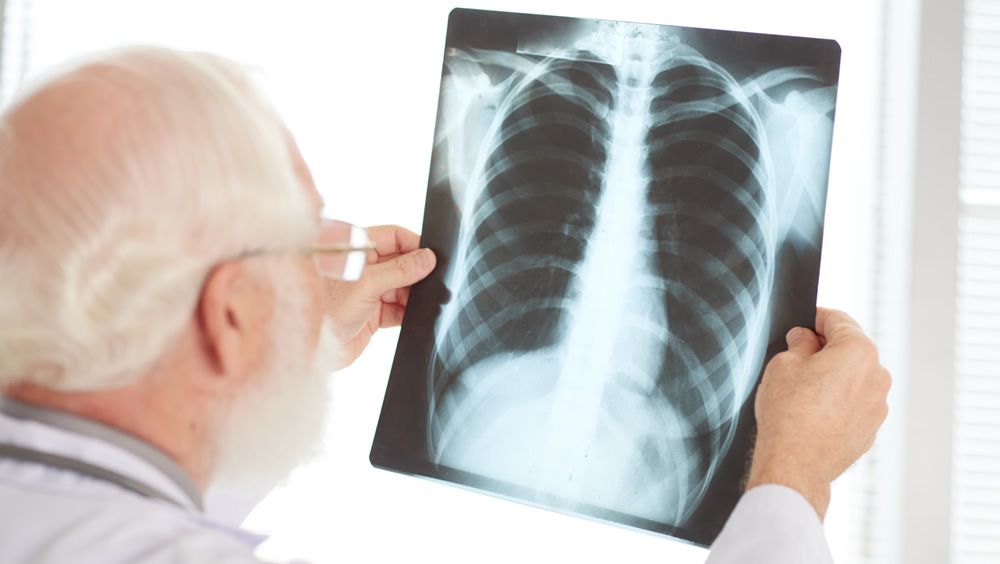

La diseminación del cáncer a los pulmones es una de las formas más comunes de metástasis en varios cánceres. Una vez allí, es extremadamente mortal y difícil de tratar.

La diseminación del cáncer a los pulmones es una de las formas más comunes de metástasis en varios cánceres